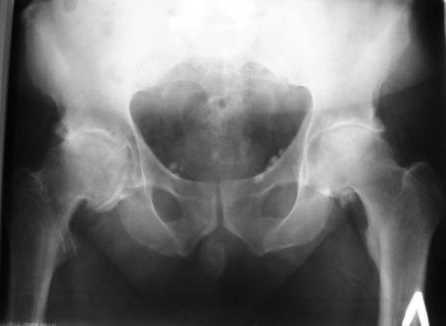

Больной Т. 56 лет, Диагноз: двухсторонний коксартроз 3-4 ст справа, 1-2 ст слева 2.10.08 выполнена операция тотальное бесцементное эндопротезирование. Использовался наружный доступ, положение на боку. Операция протекала без особенностей.

Не надо особенно мудрить, ножка вышла высоко, практически весь проксимальный отдел бедра сохранен, после аккуратного удаления ножки с максимально бережным отношением к м.тканям, и после визуализации канала используйте ту ножку, которая оптимально подходила при первичном планировании. Окончательный размер ее вы определите по плотной посадке рашпиля. Неприятно, но не смертельно... бывает хуже